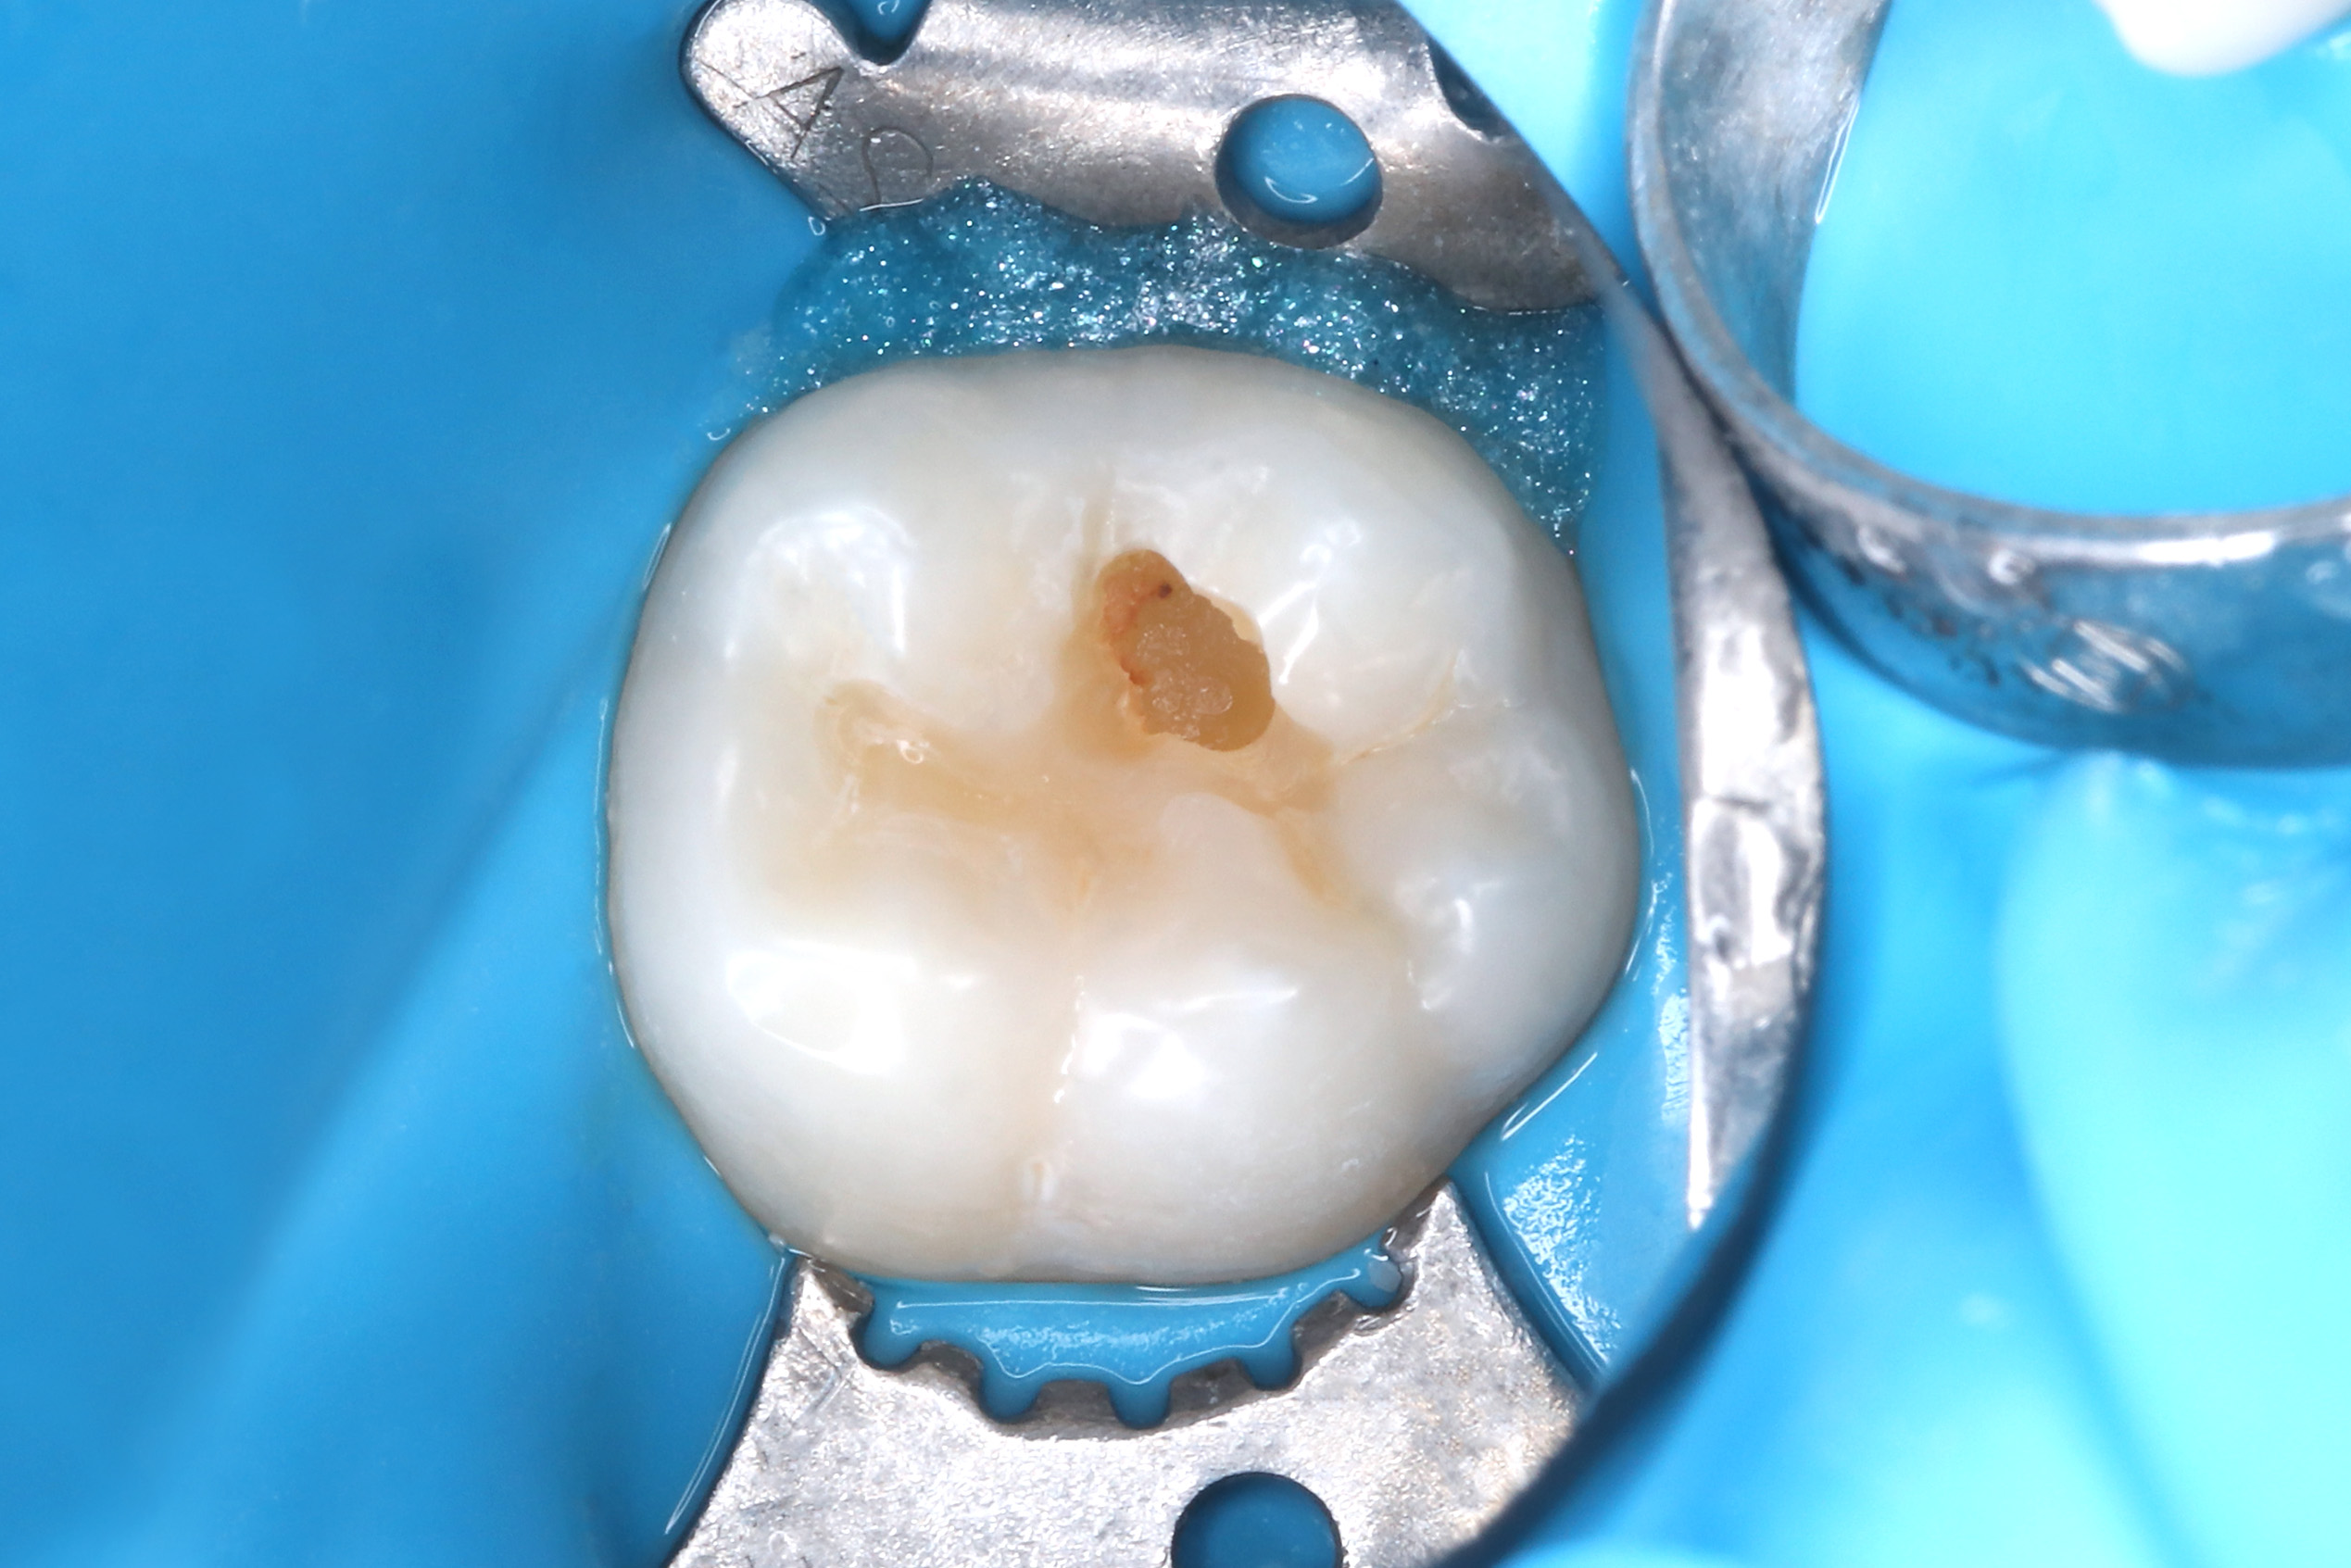

На осмотре был обнаружен кариес, жалоб на боль нет

Лечение кариеса 36 зуба, Гармонайз